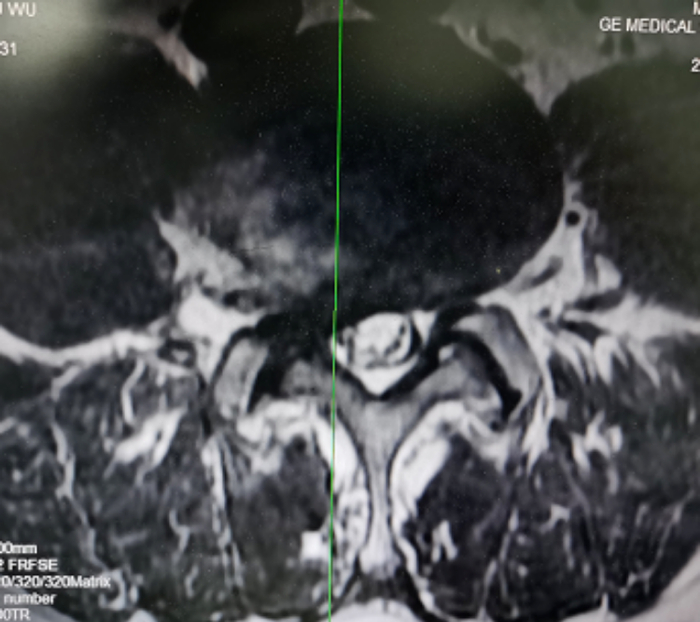

术前腰椎MRI提示:腰4/5椎间盘突出伴侧隐窝狭窄/图源 重医附三院